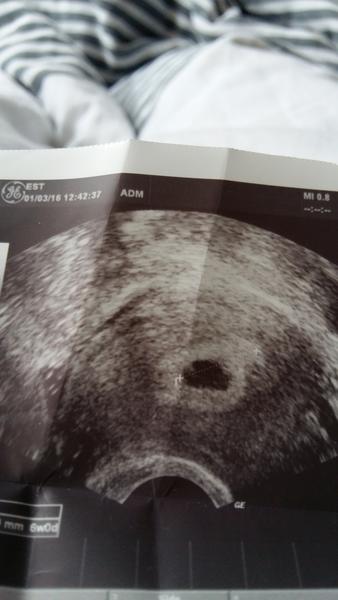

@market_s ahoj, já beru utrogestan 2-2-2 zaváděním a estrimax 1-1-2 mě menstruace nepřišla už od 14.1.2016 a 1.2.2016 jsem byla na IVF že my zaváděly oplodněná vajíčka aby se chytly teď 1.3. jsem byla na ultrazvuku a pošlu obrázek co bylo vidět . Pokud bereš utrogestan ber ho do další kontroly dokud ti Dr. neřekne že máš s tímto práškem přestat.